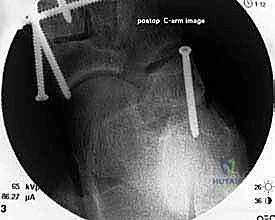

* الأشعة السينية (X-rays) مع تحمل الوزن: ضرورية لتقييم درجة انهيار القوس وزوايا العظام (مثل زاوية تالونافيكولار Meary's Angle).